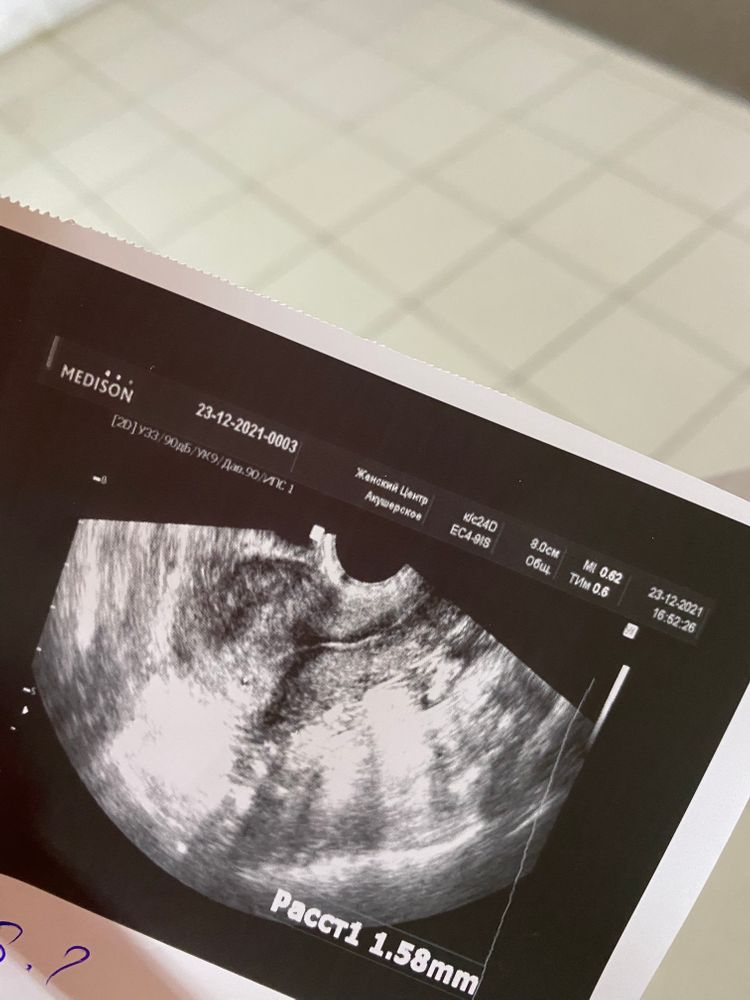

Здравствуйте! Ситуация такая. Был выкидыш 17.11, ходила на узи после - все чисто. Был незащищённый па после, сейчас 23.12 и 8 день задержки, тесты полосатые, ходила на узи, там чёрная точка 1.58мм, врач сказала, что срок 2-3 недели. Но поставила беременность под вопросом и направила сдать кровь, результат будет во вторник. У меня вопрос, может у кого такое было?